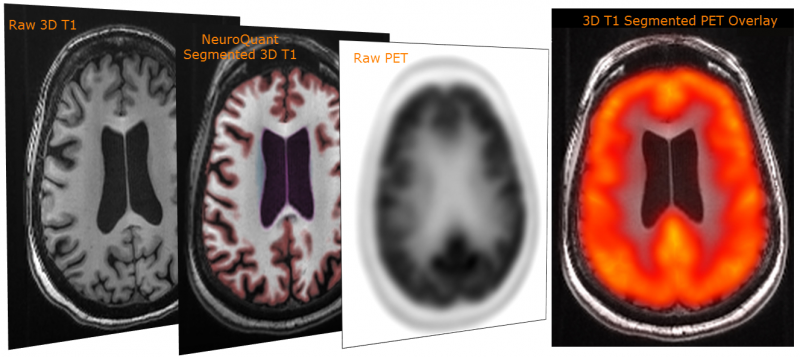

While each modality (MRI, PET, CT) has its own set of uncertainties and image artifacts, Cortechs.ai’ image distortion correction, and image consistency and reproducibility technologies eliminate a majority of the alignment problems. Additionally, Cortechs.ai’ unique, patented Dynamic Atlas™ alignment technology creates a joint coordinate system that allows image data sets from each modality to reference, facilitating, for example, MRI + PET image overlay.

PETQuant™ offers clinicians the ability to quantify subregional tracer binding in native brain space. How does it do this? Rather than providing deposition of amyloids in a template volume that might or might not correlate to the actual patient’s frontal lobe or hippocampus, NeuroQuant® provides deposition information (and norms) in volumes that are derived directly from the patient’s 3D T1 images precisely indicating relevant brain structure information for the clinician.

The patient’s native space provides the actual and accurate deposition information – not just approximates in general volumes. The patient’s native space becomes even more important when evaluating brain structure changes over time. Taking the patient’s brain structure volume changes into account allows for a more accurate amyloid deposition measurement because the associated reference volumes change appropriately.